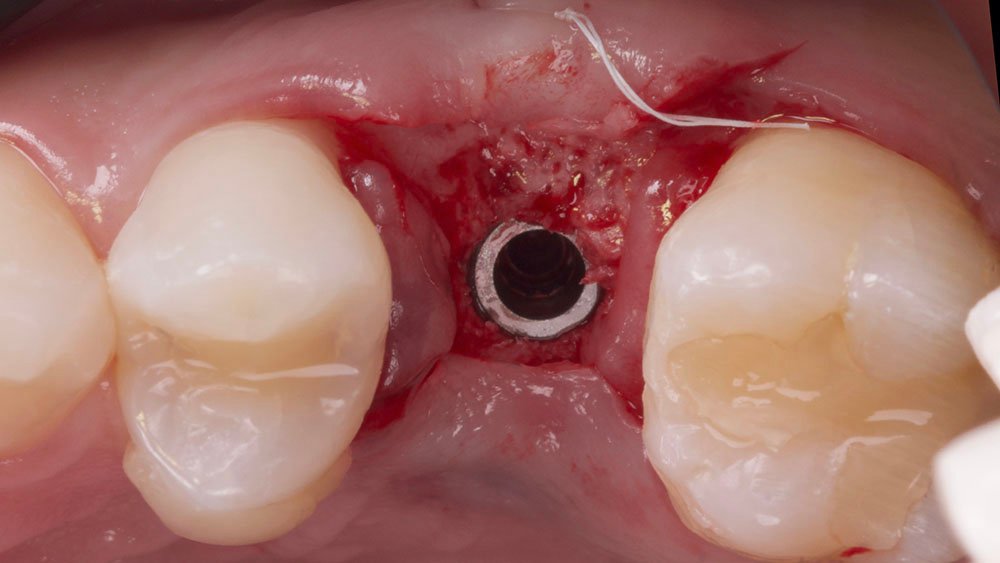

Os nervos alveolares superiores anterior, médio e o palatino maior foram anestesiados com dois tubetes de Cloridrato de Mepivacaína 2% (Cristália Produtos Químicos Farmacêuticos Ltda., São Paulo-Brasil). Com o auxílio de uma lâmina 15C (Syann Morton – Cód.11810 (HOS11810A)), foi realizada uma incisão ligeiramente palatinizada em retalho dividido, paralela ao tecido ósseo palatino, de modo a separar a porção mais epitelial do tecido conjuntivo palatino (aproximadamente 2 mm) da porção mais profunda (aproximadamente 3 mm), para que em seguida, uma segunda incisão no tecido palatino (abaixo do alçapão formado pela primeira incisão) pudesse liberar essa porção mais profunda (juntamente a periósteo) e a mesma seja rotacionada para a vestibular do defeito. Na sequência, outras duas incisões em retalho total (até periósteo) foram realizadas de modo a dar a forma das futuras papilas proximais. Uma última incisão superficial foi realizada na porção oclusal do defeito com a finalidade de desepitelização para que o tecido oclusal também fosse rotacionando para a vestibular. Para o descolamento do enxerto e mucosa vestibular foram utilizadas curetas Molt (Supremo Instrumentais).

Confeccionou-se um dente provisório aparafusado com coifa de titânio 4,5 x 4 mm – Linha Ideale (Implacil De Bortoli, São Paulo-Brasil), sobre o Pilar Ideale 4,5 x 4 x 2,5 (Implacil De Bortoli, São Paulo-Brasil), apoiado no Implante Maestro 4 x 11 (Implacil De Bortoli, São Paulo-Brasil), obtendo um torque aproximado de 40N. E por fim, realizou-se a proservação e acompanhamento radiográfico.